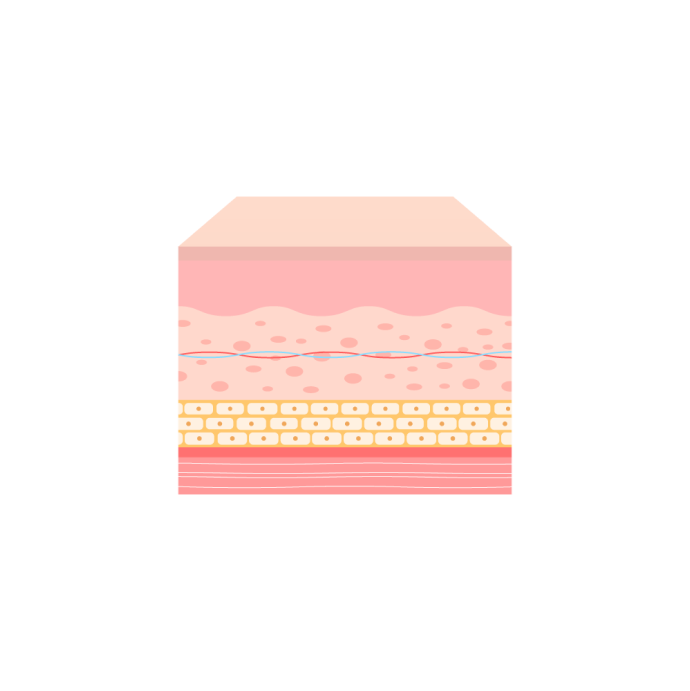

เทคนิคดูดไขมันแบบคัดแยกเฉพาะชั้นกลาง

ไขมัน! ควรเอาออกตรงไหน และควรเก็บไว้ตรงไหน?

Why?

ทำไมต้อง The LINE?

ทำไมถึงช้ำน้อย บวมน้อย และผิวตึงกระชับมากกว่า?

It เป็นเทคนิคขั้นสูงที่ปลอดภัย โดยดูดเฉพาะชั้นไขมันใต้ผิวหนังอย่างแม่นยำโดยไม่กระทบต่อไขมันที่ช่วยปกป้องผิวหนัง

ด้วยการคงไว้ซึ่งสเต็มเซลล์ ช่องว่างในชั้นไขมันจะถูกกระชับ ช่วยเพิ่มความยืดหยุ่นและการฟื้นฟูของผิวหนัง